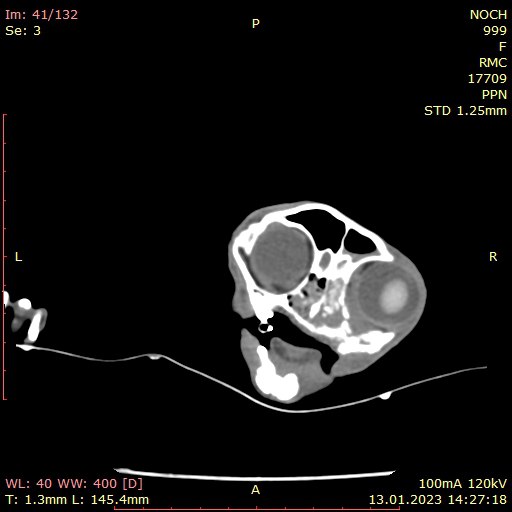

КОМП'ЮТЕРНА ТОМОГРАФІЯ - метод, заснований на отриманні пошарового рентгенівського зображення.

Тому, ми отримуємо можливість точно встановити локалізацію та поширеність патологічного процесу, а також оцінити результат лікування.